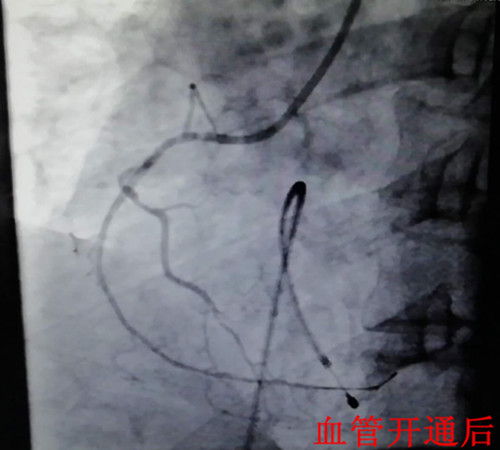

在一陣有效地搶救之后,患者在氣管插管、呼吸機輔助呼吸下,先行心臟臨時起搏器置入,后行左右冠狀動脈造影,造影顯示:右冠狀動脈呈鼠尾狀,開口5mm處100%閉塞,旋支血管中遠段60—99%彌漫狹窄病變。手術(shù)者立即開通右冠狀動脈,盡管患者在手術(shù)過程中不斷出現(xiàn)室速室顫,血壓下降,但隨著右冠狀動脈遠端血流恢復(fù),患者終于生命體征趨于平穩(wěn),安全返回監(jiān)護室繼續(xù)下一步治療。